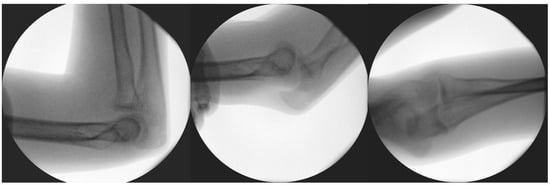

Postoperative X-rays showed the adequate position of the corticospongiosal block. After three weeks, the cast was removed and physiotherapy was initiated. After five weeks, the child complained about numbness in his ring and little fingers. At that time, his ROM was slightly limited during flexion and extension; however, his pronation–supination range was complete. Physiotherapy was continued to better the ROM of the elbow. By the third month, the joint movements were complete, with no signs of elbow instability. Control X-rays revealed signs of proper graft remodelling. By the eighth month, the fracture was healed clinically and radiologically (Figure 8).

Figure 8.

Radiographic control images from weeks 3 (A), 8 (B), 24 (C), and 40 (D).

From the X-ray imaging, it was seen that the fracture was rebuilt and the coronoid process was stabilized in a good position, with a complete ROM in the elbow joint (Figure 9).

Figure 9.

Functional images ten months after the reconstruction.